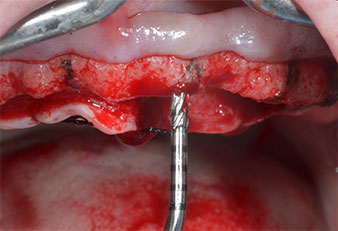

Para marcar las posiciones del implante y realizar la preparación piloto, se utilizó un inserto piezoeléctrico (Piezomed I1) con revestimiento de diamante y forma de llama (figura 3). Se tomaron precauciones para realizar movimientos hacia arriba y hacia abajo, con una potencia reducida, una irrigación completa y una baja presión (por debajo de 300 g). A continuación, se aplicó un inserto piloto (Piezomed I2A/I2P) para aumentar el diámetro inicial de 2 mm de los sitios de implante (figura 4), seguido de un inserto de 3 mm (Fig. 5).

Marcador ultrasónico Piezomed

Fig. 3: La preparación con inserto marcador ultrasónico Piezomed I1 se realizó con movimientos hacia arriba y hacia bajo, paralelos al eje longitudinal del área de trabajo.